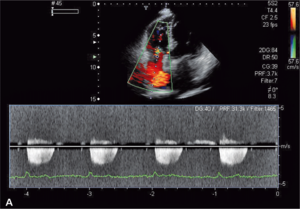

Rycina 3. Podwyższone ciśnienie skurczowe krwi w prawej komorze u chorego z toczniem rumieniowatym

układowym.

Toczeń rumieniowaty układowy

Zwiększone ryzyko zaburzeń zakrzepowo-zatorowych u chorych z toczniem rumieniowatym układowym wynika przede wszystkim z częstej obecności przeciwciał antyfosfolipidowych u tych chorych. W ostatnich badaniach wykazano, że zwiększone stężenie aCL i anty-ß2GPI w klasie IgG powodują wzrost ciśnienia skurczowego w prawej komorze (ryc. 3A, B) [11]. Stwierdzono także większą częstość występowania przeciwciał aCL u chorych z SLE i nadciśnieniem płucnym w porównaniu z chorymi z prawidłowym ciśnieniem w tętnicy płucnej [12]. W innym badaniu chorych z mieszaną chorobą tkanki łącznej (mixed connective tissue disease, MCTD) nadciśnienie płucne było związane ze zwiększonym stężeniem przeciwciał anty-ß2GPI [13]. Podwyższenie ciśnienia skurczowego w tętnicy płucnej związane z występowaniem przeciwciałami aCL może wynikać z mikrozakrzepicy lub mikrozatorowości, która zwiększa opory naczyń płucnych, powoduje wzrost ciśnienia skurczowego w prawej komorze i prowadzi do powiększenia prawej komory. Należy podkreślić, że względne ryzyko zatorowości płucnej u chorych z SLE w pierwszym roku od rozpoznania w porównaniu z populacją ogólną jest bardzo duże i wynosi 10,23 [14].